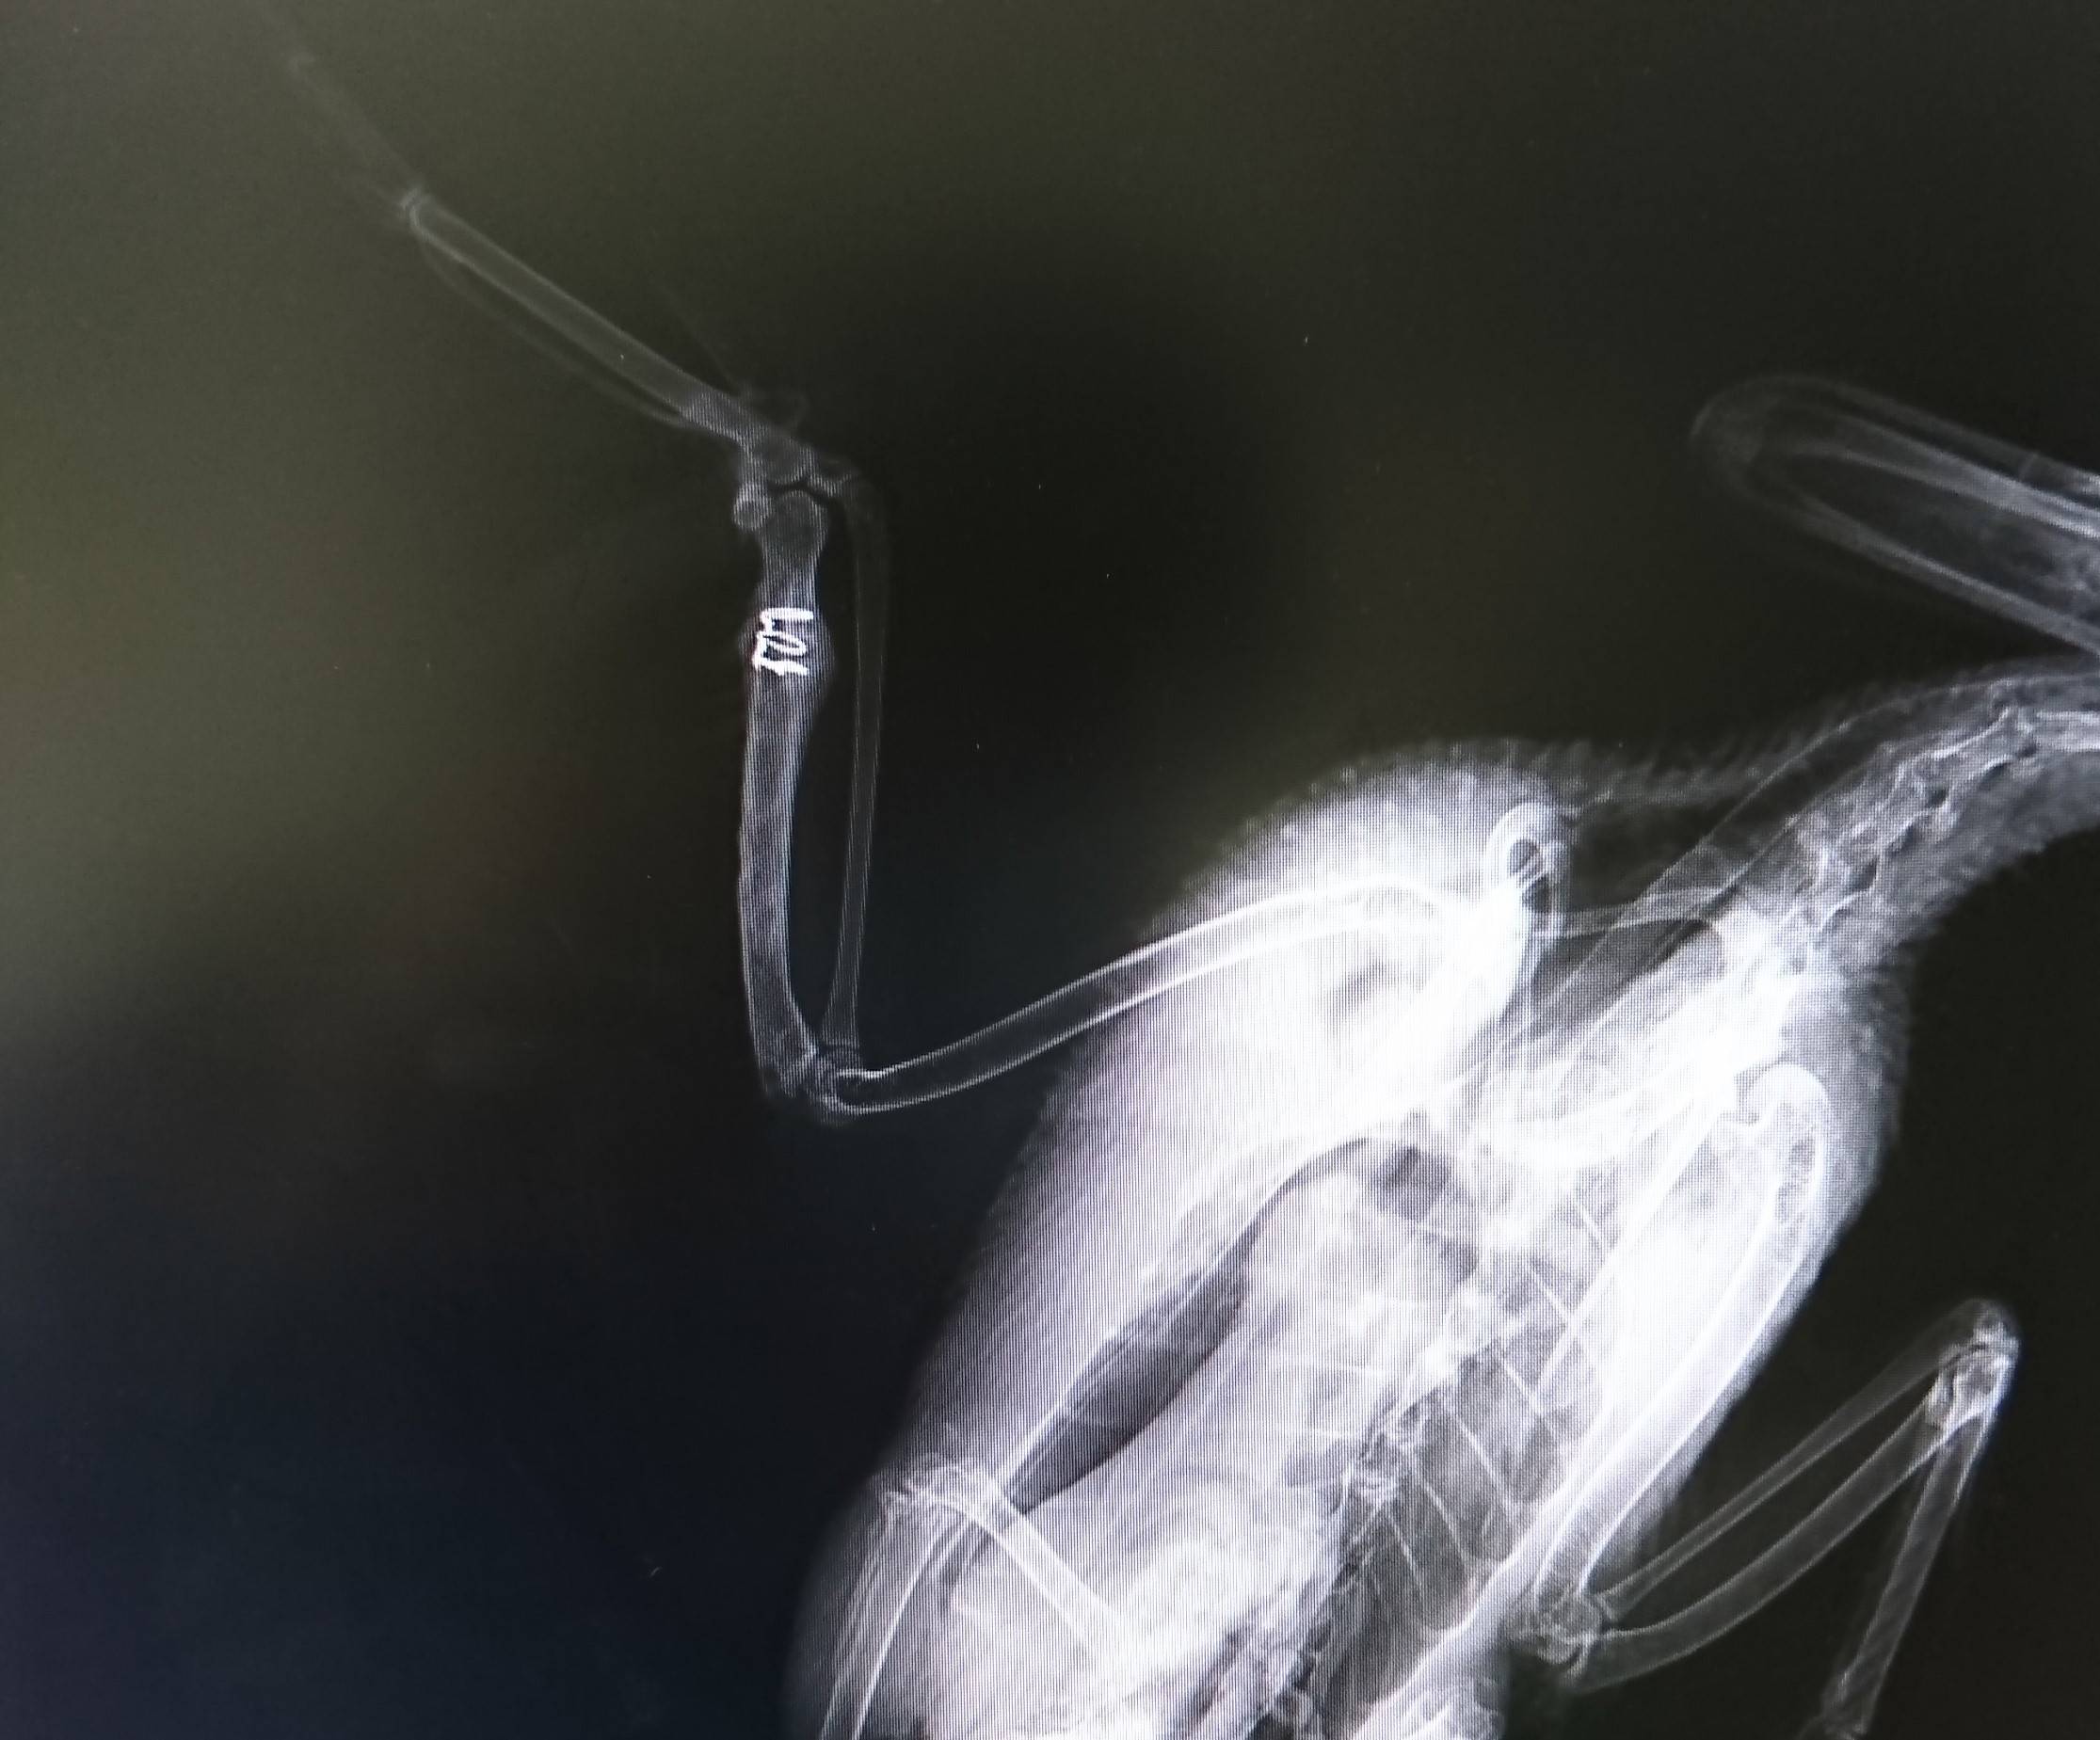

骨が増生しました。

しばらく翼を動かさなかったため、関節がかたくなってしまっているので伸ばすリハビリをします。

リハビリ前はここまでしか開きません。